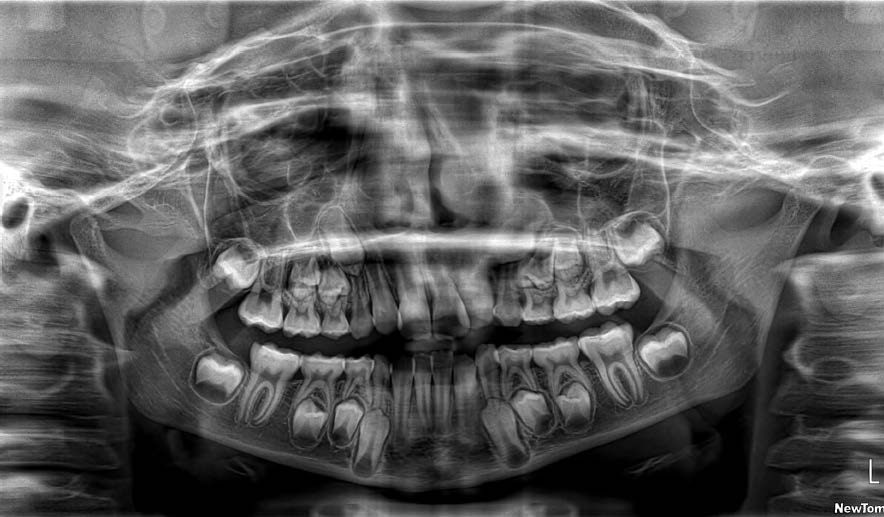

The patient presented with a skeletal Class I relationship and a mesofacial growth pattern, indicating balanced sagittal and vertical skeletal proportions. Dental examination revealed a Class I molar and canine relationship bilaterally. The patient was in the mixed dentition phase. Significant dental crowding was observed in both arches, consistent with a dentoalveolar discrepancy. Midline deviations were present, affecting dental symmetry and occlusal harmony. The maxillary lateral incisors were in crossbite, contributing to anterior transverse discrepancy and functional imbalance.

Periodontal evaluation revealed early signs of periodontal disease, primarily affecting tooth 41. Radiographic assessment demonstrated root convergence of teeth 11 and 21, indicating compromised root parallelism. Overall, the initial presentation was characterized by dentoalveolar crowding, transverse discrepancies, occlusal asymmetries, and early periodontal involvement within an otherwise favorable skeletal framework, requiring a carefully planned orthodontic approach to ensure functional stability and periodontal preservation.